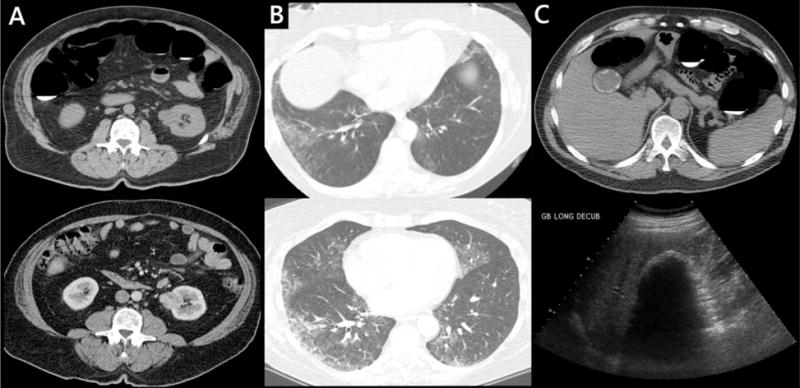

Figure 2. Unsuspected significant extracolonic findings at screening CT colonography.

A: 64-year-old man. Indeterminate renal mass (top) which enhances at follow-up contrast-enhanced CT (bottom). Later proven to be renal cell carcinoma at biopsy. B: 61-year-old nonsmoking woman. Incompletely evaluated groundglass opacity at the lung bases at CTC (top), more thoroughly evaluated at dedicated chest CT(bottom) and consistent with nonspecific interstitial pneumonia (NSIP). C: 52-year-old man. Porcelain gallbladder seen at CTC (top) and confirmed at follow-up ultrasound (bottom). The patient subsequently underwent cholecystectomy.